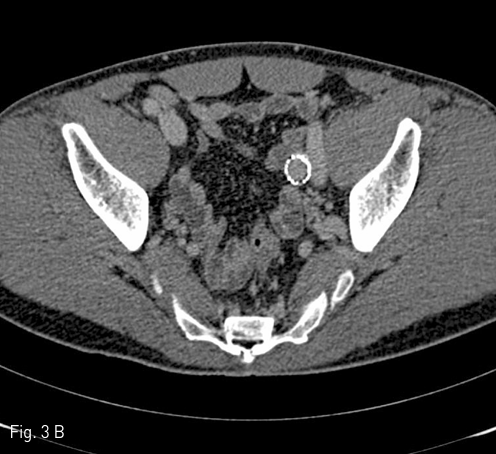

야뇨증상과 좌측 하복부 종괴에 대한 평가를 위해 시행한 CT에서 좌측 골반강에 약 5.6 X 5.2 X 7.4 cm 크기의 경계가 뚜렷하고 조영증강을 보이는 병변이 있으며, 방광의 전외측을 압박하고 있었다. 이 병변은 외장골 정맥과 연결되어 있고, 외장골 정맥과 동일한 정도의 조영증강을 보였다 (Fig. 1A). 좌측 하지에서 시행한 정맥조영술에서 좌측 외장골 정맥에서 기인하는 saccular aneurysm이 확진되었다 (Fig. 1B).

Fig 1A

(A) CT shows enhanced mass lesion associated with the left external iliac vein.